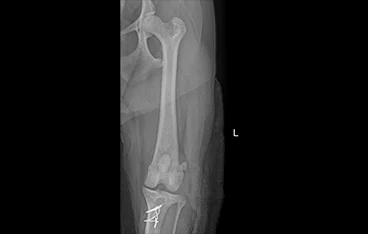

골절

골절 수복(screw, plate, k-wire, pin 등)

• PLATE

• PLATE 수술 전

PLATE 수술 후

• 복합골절

• 최소침습 골절수술